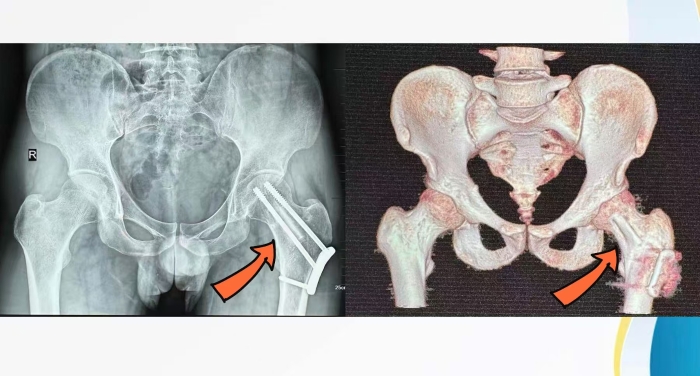

术前CT显示骨折错位